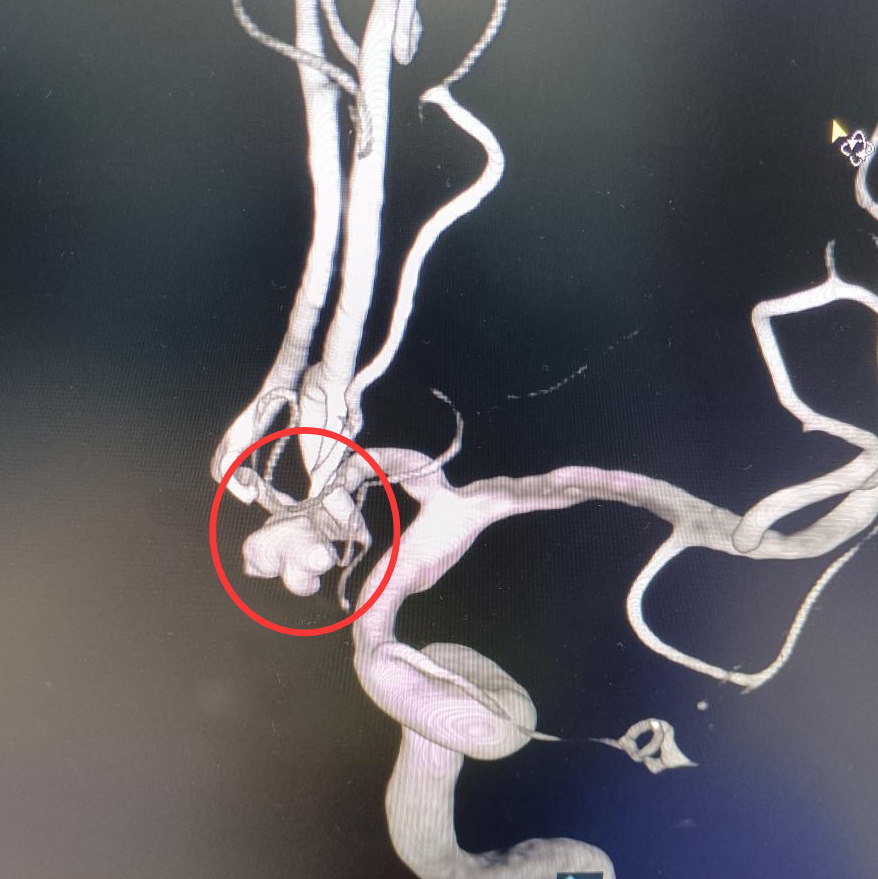

急诊医生发现他双侧瞳孔缩小,对光反射减弱。鉴于病情十分危急,医生立即启动绿色通道,在10分钟内完成了头颅CT,结果显示其蛛网膜下腔广泛出血,这是颅内动脉瘤破裂的典型表现。随后的颅脑CTA 显示,盘林的前交通动脉上有一个5毫米的不规则“泡泡”。据了解,脑动脉瘤并不是真的瘤,只是动脉血管壁鼓起的一个“小泡泡”。这种“小泡泡”被称为颅内“不定时炸弹”,一旦破裂(即脑出血),如果抢救不及时,分分钟就有可能殒命。

在造影机投射的血管 “地图” 上,神经外科副主任医师陈日朝操控着直径 0.56 毫米的微导管,从患者股动脉穿刺点出发,沿着髂动脉、颈动脉的蜿蜒路径上行。在 0.1 毫米级的血管成像实时更新下,微导管进入体内约1米左右,抵达动脉瘤腔。手术团队默契配合,将 5 枚弹簧圈填入其中完成致密栓塞。手术很成功,从确诊到完成“拆弹”仅用2小时17分钟。手术全程微创,患者大腿根部仅留 2 毫米穿刺痕迹。